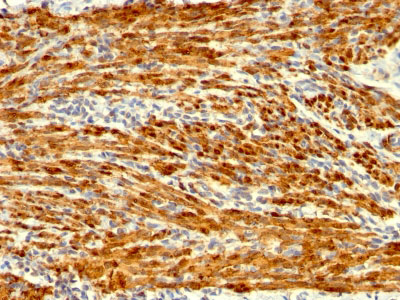

Formalin-fixed, paraffin-embedded human Uterus stained with Calponin-1 Monoclonal Antibody (SPM169). |